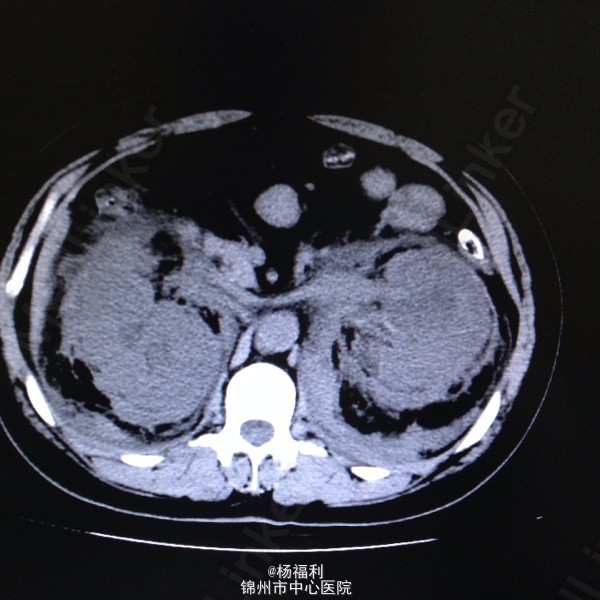

44岁女患。为消化科我会诊患者。 现病史:以上腹痛9小时为主诉入院。无发热及寒战、噁心未呕吐,无腹泻及黑便。 既往史:双眶炎性假瘤2年,口服激素治疗,并补钾。

查体:上腹部压痛,无反跳痛、右侧压痛明显,右肾区叩击痛,左肾区轻叩击痛,双输尿管走形区无压痛。 辅助检查;泌尿系彩超:双肾积水。 血白细胞:9.99*10^9。 肾功能正常。 全腹部ct及MRU检查:见图片。

诊断;真的不知道是啥病。 处理:暂时止痛处理。双肾病变。不知从哪里下手。